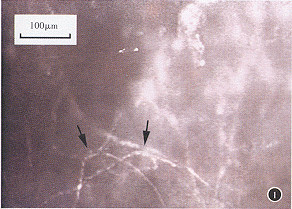

角膜老年環病理診斷比較困難,必須與細菌性角膜潰瘍進行鑑別。有農業性眼外傷史,典型的臨床表現,是診斷的主要依據。再者,疑為真菌感染時,應作角膜病變處刮片。將取下的壞死組織放於玻片上,滴5%氫氧化鉀一滴,覆蓋破片,立即鏡檢,尋找真菌菌絲。有條件時應進行真菌培養。